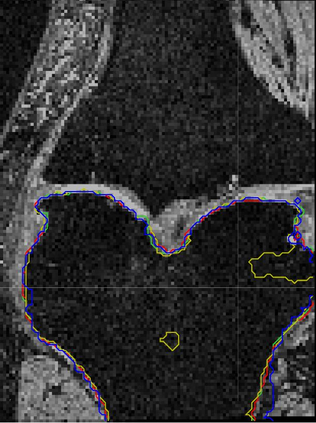

Direct automatic segmentation of objects from 3D medical imaging, such as magnetic resonance (MR) imaging, is challenging as it often involves accurately identifying a number of individual objects with complex geometries within a large volume under investigation. To address these challenges, most deep learning approaches typically enhance their learning capability by substantially increasing the complexity or the number of trainable parameters within their models. Consequently, these models generally require long inference time on standard workstations operating clinical MR systems and are restricted to high-performance computing hardware due to their large memory requirement. Further, to fit 3D dataset through these large models using limited computer memory, trade-off techniques such as patch-wise training are often used which sacrifice the fine-scale geometric information from input images which could be clinically significant for diagnostic purposes. To address these challenges, we present a compact convolutional neural network with a shallow memory footprint to efficiently reduce the number of model parameters required for state-of-art performance. This is critical for practical employment as most clinical environments only have low-end hardware with limited computing power and memory. The proposed network can maintain data integrity by directly processing large full-size 3D input volumes with no patches required and significantly reduces the computational time required for both training and inference. We also propose a novel loss function with extra shape constraint to improve the accuracy for imbalanced classes in 3D MR images.

翻译:3D医学成像的物体,如磁共振成像(MR)成像的直接自动分离,具有挑战性,因为往往需要精确地确定大量调查中大量存在复杂地理不对称的单个物体。为了应对这些挑战,大多数深层学习方法通常会大大提高其模型内可训练参数的复杂性或数量,从而提高其学习能力。因此,这些模型一般需要在运行临床MR系统的标准工作站上花很长的推断时间,并限于高性能的计算机硬件,因为它们的记忆要求很大。此外,要在这些大型模型中安装3D数据集,还要利用有限的计算机记忆,经常使用交换技术,例如补对称培训等,以牺牲从对诊断目的具有临床重要性的投入图像中获得的精细比例的几何地理信息。为了应对这些挑战,我们提出一个具有浅度记忆足迹的银色网络,以有效减少为状态性能所需的模型参数数量。这对于实际就业至关重要,因为大多数临床环境只有低端硬件,计算机功能和记忆有限。拟议的网络可以通过直接处理全尺寸三维化技术来保持数据的完整性,直接处理全尺寸的全尺寸三维的图像,从而大幅改进所需的超度变压的磁度计算。